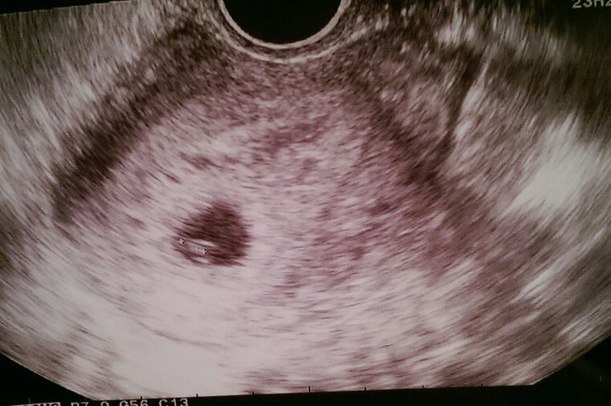

Во мне бьются два сердечка!

Моя бусинка на фото больше похожа на маленькую мушку)))

КТР 4,1мм

желточный мешочек 23 мм

размер ПЯ 13,2мм

Все у нас соответствует сроку 5-6 недель

Сердечко не услышали, но узистка сказала, что эмриончик пульсирует - живой )))